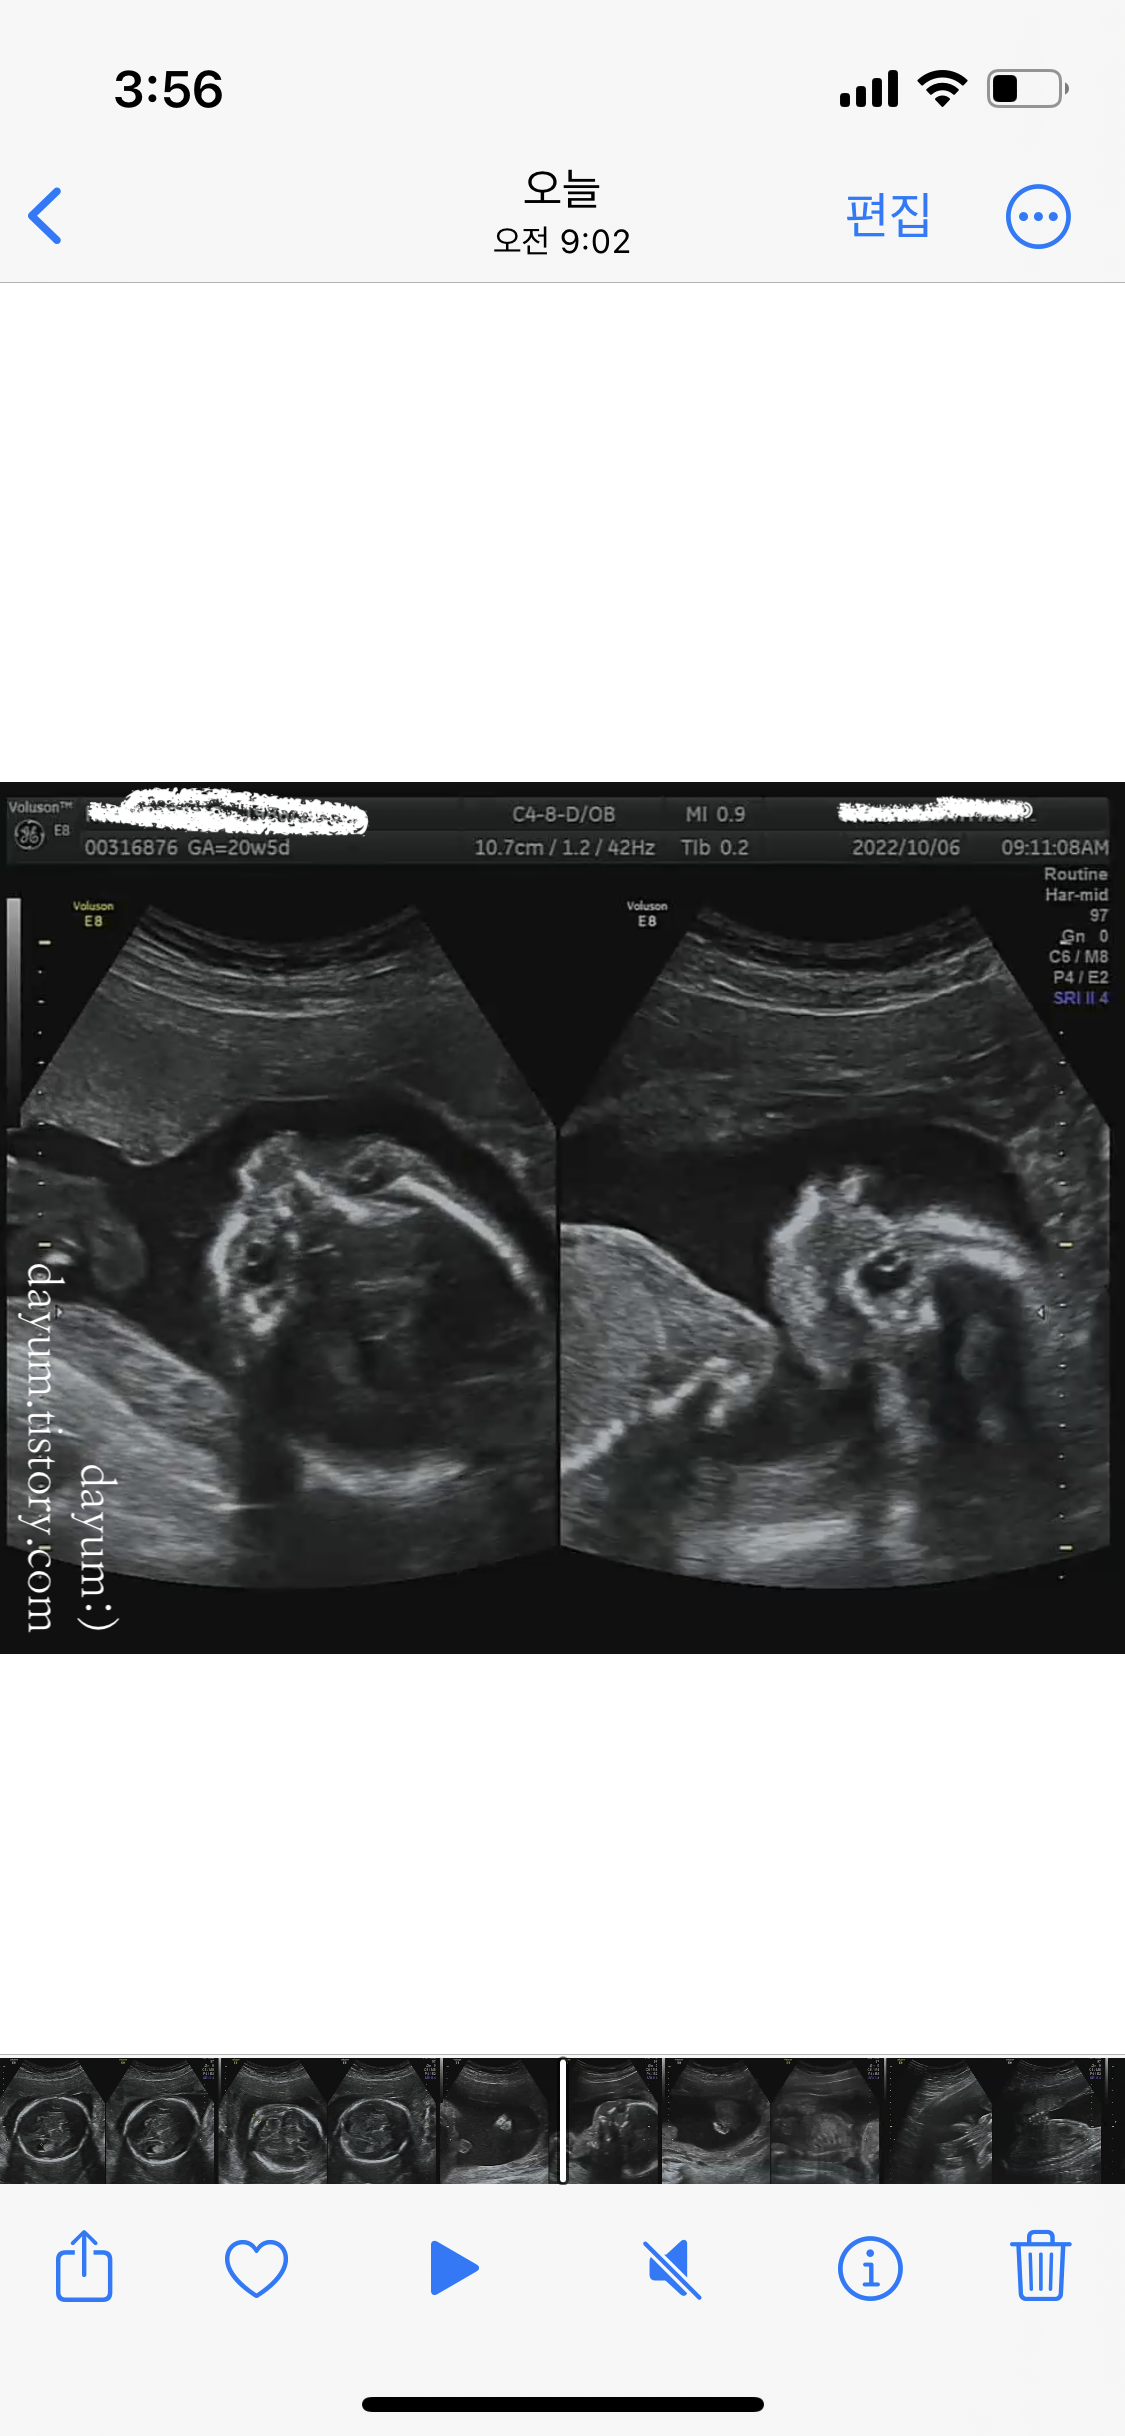

보통 20-30분이면 된다는데 이번에도 조이가 잘 협조해줘서 금방 끝났다.

녹화기록을 보니 11분 정도 녹화되어 있었다. 엄청 빨리 끝난편... 처음에 옆으로 고개를 돌리고 자고 있어서 얼굴을 잘 안보여주다가 마지막에 자다가 깨서 얼굴도 봤다.

초음파선생님이 머리둘레부터 언청이 확인, 뇌모양, 손가락, 발가락, 배둘레, 심장, 위 등 생성된 장기들을 설명해주시고, 탯줄에 혈액이 잘 들어가는지, 자궁은 괜찮은지, 양수의 양과 경부길이까지 싹다 훑어주셨다.

조이는 모두 정상범위로 잘 자라고 있고, 초음파상 정상이라고 한다.

이번에는 정밀초음파로는 내부 장기의 발달, 기형이나 장애를 확인하는 거고 입체초음파로는 외형적인 모습을 확인하는 거라고 한다.